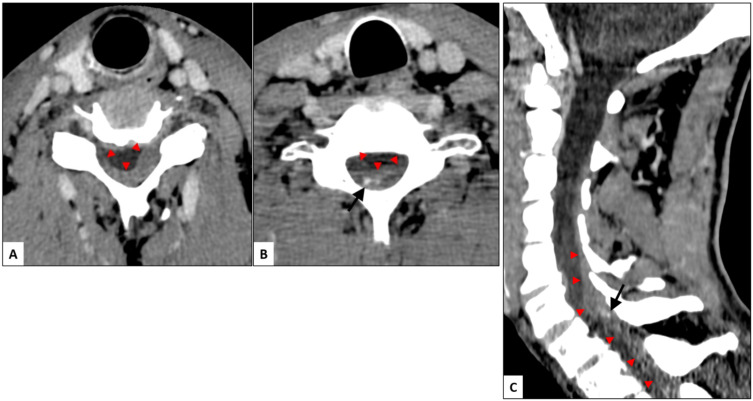

自发性脊髓硬膜外血肿(SSEH)是一种罕见的病理,对患者有潜在的严重后果。由于其罕见的发病率和频繁的非典型表现,SSEH很容易被误诊。抗凝或抗血小板治疗与SSEH之间的关系已在多个病例报告和文献综述中得到描述。我们报告一例61岁男性患者,接受抗凝和抗血小板治疗(分别为利伐沙班和氯吡格雷),诊断为脊柱SSEH,经椎板切除术和血肿清除后恢复良好。然而,SSEH的治疗指南很难找到,并且没有明确的抗凝和抗血小板治疗管理策略。本报告的目的是强调在选定病例中快速诊断和手术治疗的重要性,并对这些患者的抗凝和抗血小板管理及其预后提供见解。

Spontaneous spinal epidural hematoma (SSEH) is a rare pathology with potentially severe consequences for the patient. Given its uncommon incidence and frequent atypical presentation, SSEH can easily be misdiagnosed. The association between anticoagulation or antiplatelet therapy and SSEH has been described in multiple case reports and literature reviews. We present a case of a 61-year-old man on anticoagulation and antiplatelet therapy (Rivaroxaban and Clopidogrel respectively), diagnosed with spinal SSEH with good recovery after laminectomy and hematoma evacuation. However, treatment guidelines for SSEH are difficult to find and there is no clear strategy about management of anticoagulation and antiplatelet therapy. The aim of this report is to highlight the importance of rapid diagnosis and surgical therapy in selected cases and to give an insight on the anticoagulation and antiplatelet management in these patients and their prognosis.